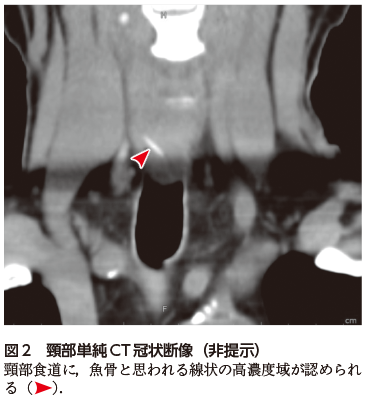

• A1:頸部食道内に線状の高濃度域が認められる(図1図2).形態や濃度からは魚骨と考えられる.

高齢者が誤飲する異物として,魚骨のほか,PTPシート(薬剤の包装)や義歯が有名である.いずれのケースも,疑われた場合はその有無および位置を確認するためにCTが施行されることが多い.魚骨は一般的にCTで線状の高濃度域として描出される.一方,誤飲異物として頻度が高いPTPシートもCTで検出可能だが,材質によっては高濃度を呈さないものもある(2020年5月号の本コーナー参照).食道だけでなく,胃や大腸にまで達することもあり,その場合は広範囲を念入りに検索する必要がある.

何らかの異物を誤飲した場合,特に飲み込みなどに際して咽頭あたりの違和感,詰まり感,痛みがしばしば認められ,本例のように受診する.CTなどで異物の残存が確認された場合,次のステップ(内視鏡を用いた除去術など)に進むことができる.しかし,画像的に異物が発見できなかった場合が問題となる.食道異物に限らず,「病気が存在しないと診断すること」は,異常を同定するよりもはるかに難しい.異物が食道や咽頭に残存していなくても,異物感だけは残存している場合もあり,心配になって受診するケースもあるだろう.頻度が高い疾患ではあっても,特に頸部CTに不慣れな若手医師では,正常構造と異物の判別に苦慮することも多い.見逃しを避けるためには,日頃から頸部の画像解剖にも慣れておいたり,骨ウィンドウやMPR像(再構成画像)を活用するなどの訓練が不可欠である.

図2